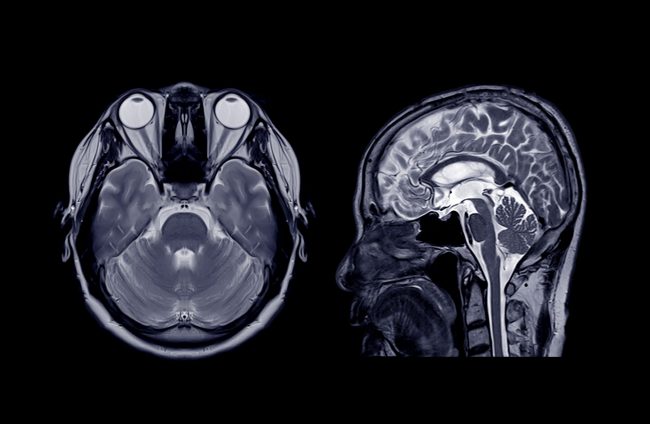

MRT

Die Magnetresonanztomographie (MRT) ist ein modernes, komplett von Röntgenstrahlen freies Untersuchungsverfahren. Ganz besonders geeignet ist dieses Verfahren für die Abbildung der Weichteilstrukturen des Körpers (Gehirn, Rückenmark, Sehnen, Muskeln, Bandscheiben, Leber, Nieren, Bauchspeicheldrüse, Milz, etc.) Auch knöcherne Strukturen wie Wirbelkörper, Gelenke und ihre Anteile wie Meniskus im Knie und Bänder der Gelenkkapseln sind sehr gut abbildbar.…